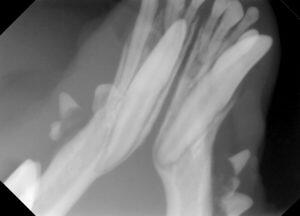

3.麻酔をかけて歯科レントゲンで確認すると、顎の中に永久犬歯が埋伏していました。